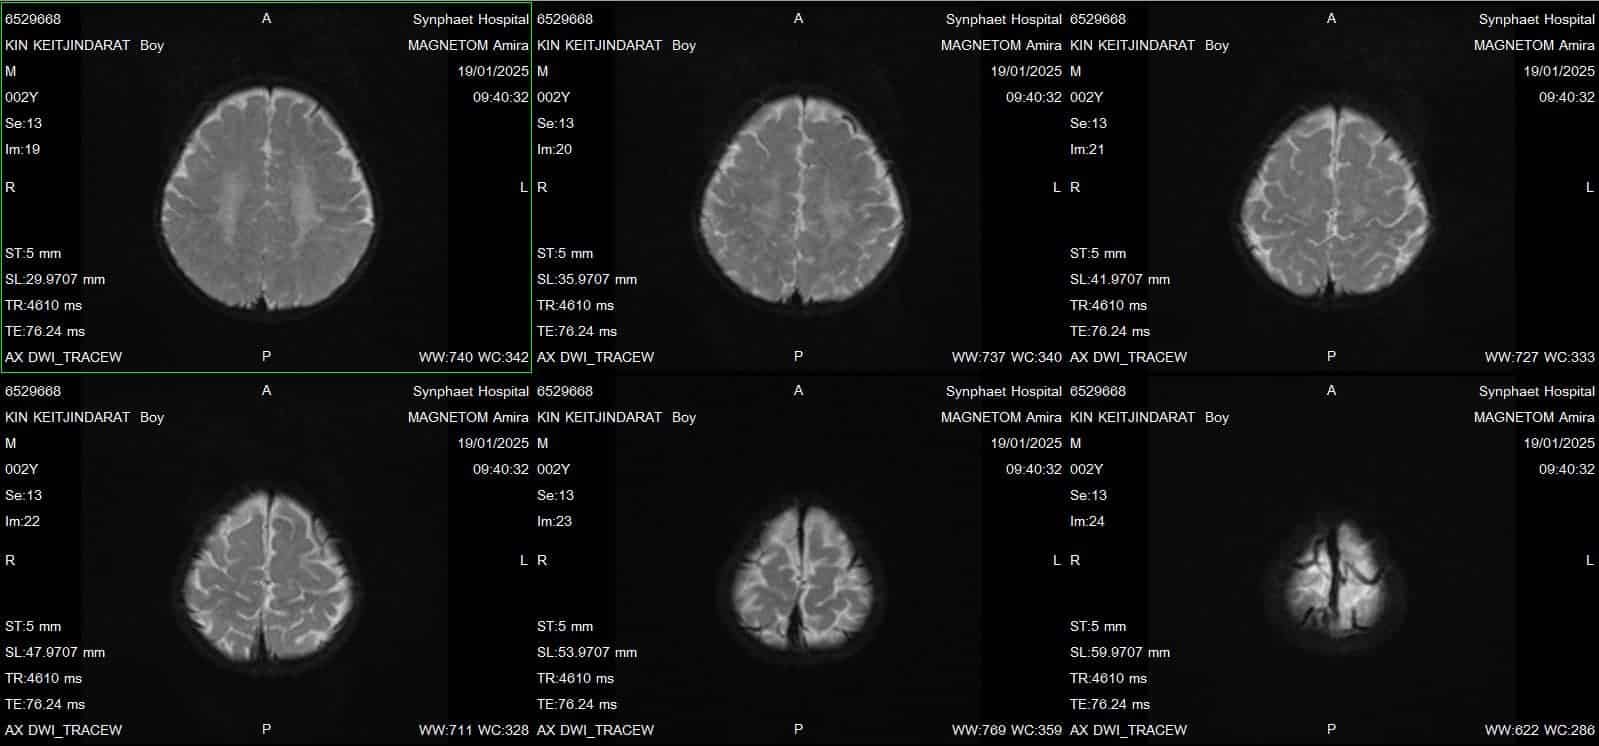

คุณหมอให้แม่ผมตรวจ MRI สมองอีกครั้ง และตรวจเลือด Genes Genetics เพื่อเป็นการตรวจหาความผิดปกติทางพันธุกรรม เพราะขาแขนผม ตึงเกร็งมากขึ้นเรื่อยๆ แถมร่างกายของผมยังทำอะไรได้น้อยลงมากๆ เหมือนเด็กอายุแค่ 4-6 เดือนเท่านั้น

• ผมใช้เวลาตรวจอยู่ร่วมปี พี่ ๆ อยากรู้มั้ยครับ ว่าผมเป็นอะไร ผมป่วยเป็นโรค MLD ครับ เป็นโรคพันธุกรรมที่หายากมากๆ ชื่อว่า Metachromatic Leukodystrophy